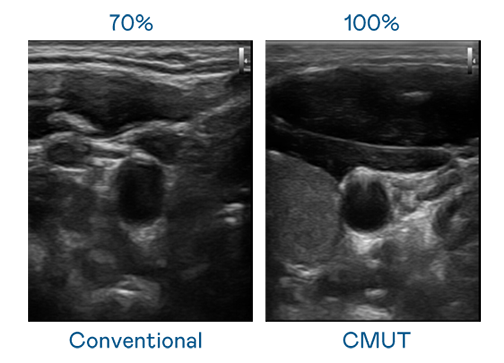

CMUT 技术是一种用电容式微机电元件来产生超音波讯号的技术。与传统 PZT 压电式技术相比,CMUT 频宽增加 30%,更宽频的超音波讯号让影像解析度大幅提升,是实现高影像品质医疗超音波扫描、促进精准医疗发展的关键技术。

大频宽带来超清晰影像

超音波影像的解析度高低,首先取决于探头能发出的讯号频宽。九游 CMUT 可提供高清晰的超音波讯号,提供高频宽、高灵敏度、影像纹理细节更高的超音波影像,协助医护人员缩短影像判读时间及利用精准的医疗影像进行诊断。